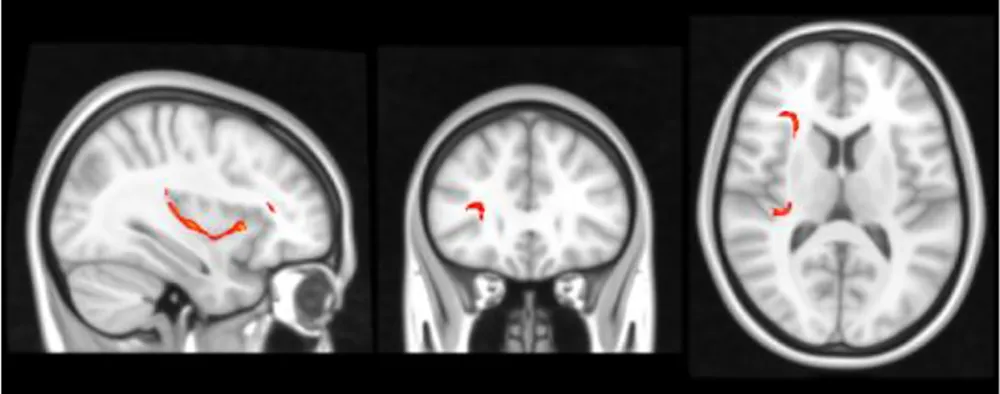

Figure 1 displays the tractography results depicting the network of tracts emanating from the seeds detailed in Table 2, which we have termed ‘Inhibitory Control Network’, incorporating tracts from seeds of both prospective withholding (rows A and B of Figure 1) and reactive inhibition phases (row C of Figure 1) of the f-MRI difference map, as well as the tracts between these and the needed waypoints. Images are oriented as per radiological convention (left side of the brain displayed on the right). In the right hemisphere, tracts were found between the following: inferior frontal gyrus (IFG) to superior temporal gyrus (STG), STG to posterior cingulate, posterior cingulate to IFG, posterior cingulate to the anterior cingulate cortex (ACC), IFG to caudate, and caudate to posterior cingulate. Connectivity did not occur as predicted between ACC to IFG. The association tract identified was the right inferior fronto-occipital fasciculus (IFOF) connecting IFG, STG, caudate, and posterior cingulate nodes. Although there was no direct connectivity between right IFG and ACC seeds, the IFOF connected IFG to the posterior cingulate waypoint, and the posterior cingulate connected to the right ACC via the cingulum. In the left hemisphere, valid tracts were found from insula to caudate, insula to inferior parietal (IFP), insula to middle temporal lobe (MTL), insula to posterior cingulate, ACC to caudate, caudate to posterior cingulate, caudate to MTL, and caudate to IFP. Connectivity was not found between insula and ACC. The majority of the association tracts in the left hemisphere belonged to left superior longitudinal fasciculus (SLF), left IFOF, and cingulum. The SLF tract connected insula, IFP, and MTL nodes, whereas the IFOF connected insula and posterior cingulate. Finally, the SLF tract was also found to connect the reactive inhibition seeds, these being, right middle frontal gyrus to caudate and right medial frontal gyrus to caudate.

Figure 1

White matter tracts of interest within ‘the inhibitory control network’. (A) Right cingulum association fibers shown in sagittal view. Anterior corona radiata, thalamic radiations, and internal capsular projection fibers in coronal view. Inferior fronto-occipital (IFOF), IFG, and STG white matter association fibers shown in axial view. (B) Left Superior longitudinal (SLF) association fibers are shown in sagittal and axial views. Corona radiata and internal capsular fibers in coronal view. Cingulum tracts are seen in coronal and axial views. (C) Tracts connecting BA 8 and BA 6 to caudate seeds from the reaction inhibition seeds. Right SLF is shown in all orientations, while posterior corona radiata fibers are shown in coronal view, and middle frontal gyrus white matter in axial view.